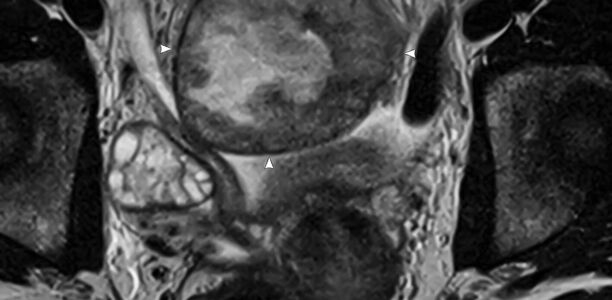

15-jähriges Mädchen mit subakuten Bauchschmerzen und erhöhten Infektzeichen